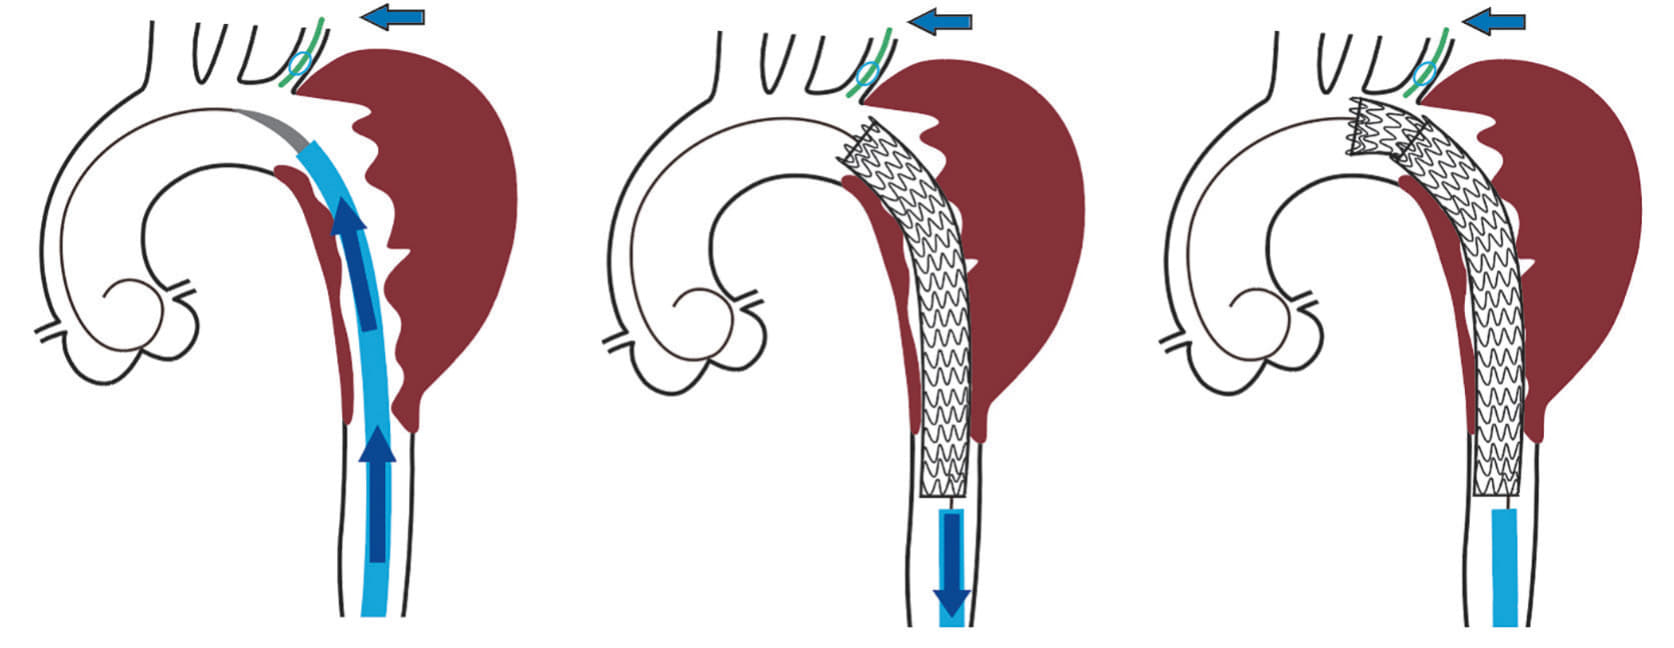

高度粥状硬化を伴う大動脈病変(shaggy aorta)に対して胸部大動脈ステントグラフト内挿術(TEVAR)を行う際は塞栓症をいかに避けるかが重要なポイントとなる。体外循環回路や血栓回収フィルターを用いた方法も報告されているが1,2、高度な技術を必要とする。当科では65 cm ゴア® ドライシール フレックス イントロデューサシースを用いて2本のゴア® TAG® コンフォーマブル 胸部大動脈ステントグラフト アクティブコントロールシステムを「Stepwise」に留置していく方法(Minimal manipulation approach:図1)を行うことで塞栓症の予防に努めており3、これを紹介する。

右大腿動脈から6 Frシースを挿入後、上行大動脈までカテーテルを進め、ガイドワイヤーを硬質ガイドワイヤー(EGoist、 Ultimate、 Arch Curve、Medicos Hirata)に交換した。65 cmドライシール フレックス イントロデューサシースをゆっくりと先進させ、大動脈の頂部近くにダイレーターの先端が到達したところまで挙上する(図3a)。

その後にシース外筒のみを約3 cm弱ほど挙上させると大動脈頂部近くまでドライシール フレックス イントロデューサシースが到達する。約3 cmまでであればシース外筒とダイレーターとの段差なく進めることが可能である(図4a, b)。

ドライシール フレックス イントロデューサシース内に1本目のTAG® コンフォーマブル ステントグラフト(TGM343410J)を挿入し、ドライシール フレックス イントロデューサシースをEVAR時のように抜退して(図 3b)、大動脈頂部(Zone 3近く)から末梢のランディングゾーンまでステントグラフトでカバーするように静かに展開する。シースとステントグラフトで「 鋪装 」された経路を通して中枢用の2本目のTAG® コンフォーマブル ステントグラフト(TGMR404015J)をZone 2まで先進させ、左鎖骨下動脈バルーンプロテクション下にゆっくり展開して、予定したデバイスを留置した(図5a, b)。

本症例で用いたアプローチでは表面が平滑なドライシール フレックス イントロデューサシースを治療予定部近くまで進めておき、粥状硬化の強い近位下行大動脈の大部分を「Windsock effect」が少ないと思われるTAG® コンフォーマブル ステントグラフトでカバーすることで壁在血栓とシース又はデバイスの摩擦を最小限とすることが狙いである。エビデンスはないが、TAG® コンフォーマブル ステントグラフトの独特の展開様式(末梢側から展開するので粗大な塞栓子は末梢に飛散しない)も塞栓症予防には有利になると考えている。